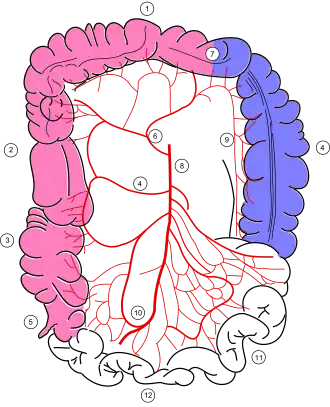

Colonic blood supply (Middle colic artery is #6) | |

The middle colic artery is an artery of the abdomen; a branch of the superior mesenteric artery distributed to parts of the ascending and transverse colon. It usually divides into two terminal branches - a left one and a right one - which go on to form anastomoses with the left colic artery, and right colic artery (respectively), thus participating in the formation of the marginal artery of the colon.

The middle colic artery supplies the superior/distal part of the ascending colon and right/proximal two-thirds of the transverse colon.[1]

The middle colic artery passes anterosuperiorly between the layers of the transverse mesocolon just right of the midline before dividing into left and right terminal branches.[2]

The anastomotic arches formed by the left and right branches of the middle colic artery are about two fingers' breadth from the transverse colon, to which they distribute branches.[3]

The sequence of anastomoses of the branches of the middle colic artery constitutes part of the marginal artery of the colon.[1]

The left branch anastomoses with a branch of the left colic artery (in turn a branch of the inferior mesenteric artery[4]) near the left colic flexure,[2] forming the arc of Riolan.[4]

The right branch anastomoses with the ascending branch of the right colic artery.[2]

In a right hemicolectomy to remove the caecum and the ascending colon, the right branch of the middle colic artery is ligated and removed.[1][6] In a transverse hemicolectomy, the entire middle colic artery may need to be ligated and removed.[6]